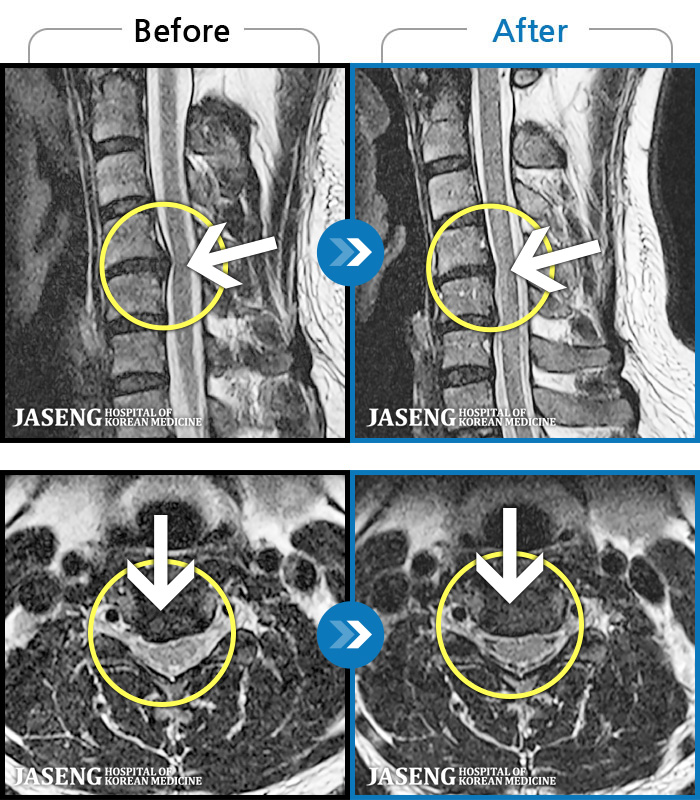

ȯںп  Ǹ   ǿ ԿǾ, ο  ġ  ۿ     Ƿ   ġḦ Ͻñ ٶϴ.